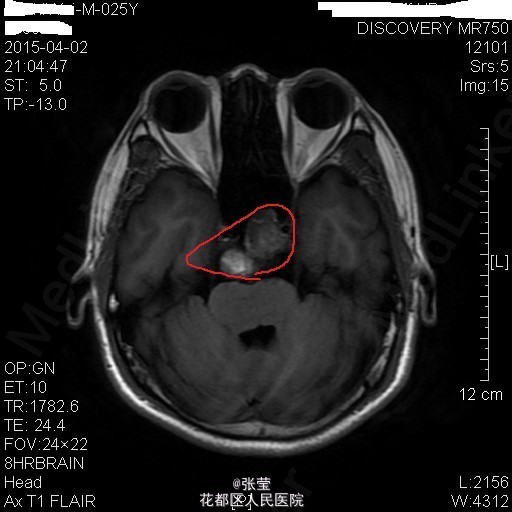

青年男性,主诉:头晕伴肢体乏力1周。 现病史:患者1周前始无明显诱因反复出现头晕,伴左侧肢体乏力、行走不稳,偶伴头痛、恶心感,休息后可稍缓解,无呕吐,无天旋地转感,无晕厥,无伴听力、记忆力减退等,发作无明显规律。至当地医院就诊,头部MR结果示:右间脑下方-脑干-桥前池-左鞍底区肿瘤,并瘤内卒中。

查体:神清,对答切题,双瞳等大等圆,直径约3mm,对光反射灵敏,双侧听力粗测正常,四肢肌力Ⅴ级。生理反射存在,病理征未引出。 辅查:颅脑MR:1、斜坡区占位,侵及中脑、脑桥右份及蝶窦,病灶ADC值增高,FA值下降,考虑脊索瘤并囊变、出血可能大。 2、MRA示双侧颈内动脉向外侧移位,余脑动脉未见明确异常。

患者入院后完善相关检查,排除手术禁忌症,于2015年4月7日行"神经内镜下经鼻蝶入路斜坡脑干占位病变切除+鞍底重建+左下腹脂肪取出术",手术顺利。 术后病理示:脊索瘤。 予抗感染、护胃、化痰、维持水电解质平衡及加强营养支持治疗,患者病情较前明显好转。